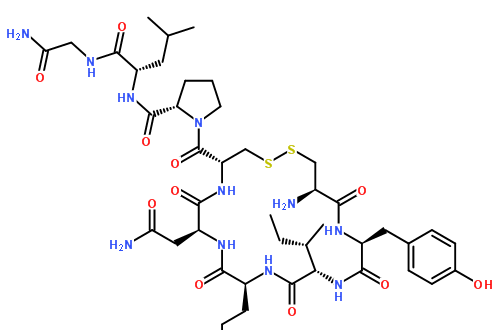

催产素(oxytocin)催产素是一种激素作用于体内器官(包括乳房和子宫),作为大脑中的化学信使,控制生殖系统的关键方面,包括分娩和哺乳,以及人类行为的各个方面。...